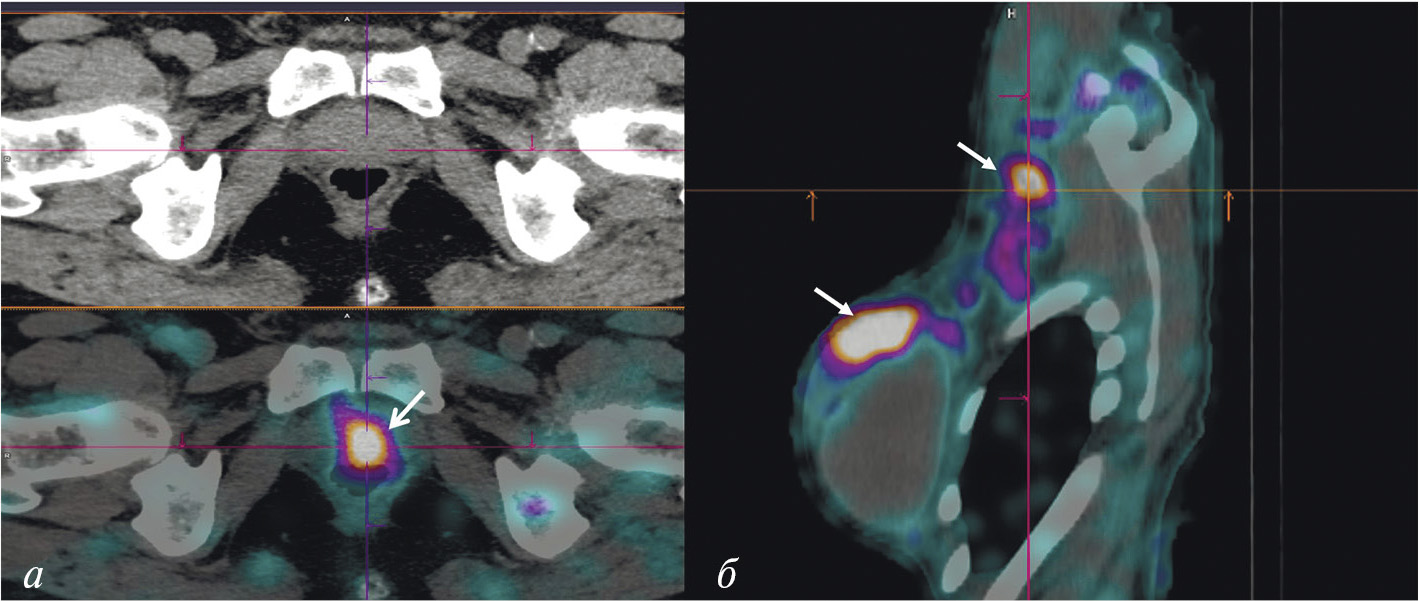

К настоящему времени создан ряд специфичных для GRPR радиоактивных индикаторов, которые подразделяются на агонистов и антагонистов гастрин-высвобождающих рецепторов. Считается, что антагонисты весьма перспективны в качестве основы для разработки радиофармацевтических лекарственных препаратов. Их преимущество заключается в отсутствии побочных эффектов, характерных для агонистов и обусловленных запуском клеточных сигнальных путей. Более того, плотность сайтов связывания антагонистов выше, чем у агонистов, что приводит к лучшему соотношению накопления препарата в опухоли и нормальной ткани. На базе антагониста GRPR разработан 99mТс-RM26 для ОФЭКТ/КТ-диагностики рака простаты и молочной железы. Клинические испытания этого препарата, выполненные в НИИ онкологии Томского НИМЦ, подтвердили возможность его применения для визуализации этих типов рака (рис. 5) [31, 32].

Рис. 5. ОФЭКТ/КТ с 99mТс-RM26 пациентов с раком простаты (а) и раком молочной железы (б) Стрелками обозначено накопление РФЛП в опухоли и лимфогенном метастазе

Имеющиеся в арсенале радиологов радиофармацевтические лекарственные препараты для визуализации СЛУ отличаются невысокой аккумуляцией (1.5–2% от введённой дозы). Поэтому в НИИ онкологии Томского НИМЦ и ТПУ был разработан оригинальный РФЛП на основе гамма-оксида алюминия “Сентискан, 99mТс” с высокими (около 12% от введённой дозы РФЛП) уровнем накопления в сторожевых лимфатических узлах [46]. Набор для его приготовления получил регистрационное удостоверение. Клинические испытания показали оптимальную фармакокинетику этого индикатора для интраоперационного выявления СЛУ и высокую эффективность при хирургических вмешательствах в случае рака шейки матки, рака эндометрия и злокачественных новообразований молочных желёз (рис. 9) [47, 48].

Рис. 9. ОФЭКТ/КТ пациентки с раком правой молочной железы после паратуморального введения РФЛП “Сентискан, 99mТс”